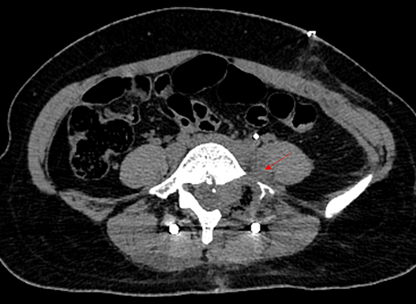

患者21岁女性,因左下腹隐痛2月,检查发现左腰骶椎前占位4天来诊。入院后进一步完善影像学检查提示左侧L5/S1椎间孔及椎体前后方占位。病灶钻缝生长,延伸至椎管内,再沿L5左侧横突孔向后伸至脊柱旁,横突孔增宽增大,骨质变薄,邻近肠管、左侧髂总血管稍推压移位。穿刺活检结果提示神经鞘瘤。

图片 7.png

图片 8.png

因肿瘤成哑铃状跨越椎体前后方,手术需行前后联合入路,前方入路需面对髂血管、输尿管等重要结构,后方则有脆弱的脊髓及神经根,对手术技巧要求极高,并且需要手术医生掌握大量的解剖学知识。经过充分的术前准备及术中的精细操作,完整切除肿瘤并重建脊柱稳定性。术后患者下肢功能未受影响,复查腰椎正位片示内固定稳定在位,CT示肿瘤已完整切除。